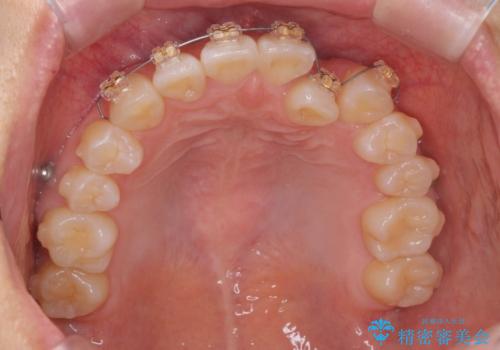

正中のズレ、引っ込んだ前歯の矯正

- 噛んだ時の前歯正中のズレ、引っ込んでいる前歯を治したい。と矯正治療を希望され来院されました。

左上2の前歯はスペースが足りないため、後方に引っ込んでしまっている状態です。

マウスピース矯正システムインビザラインで歯の後方移動、咬合関係の修正を行ったのち、引っ込んでいる左上2をワイヤーを用いて短時間で引き出す治療計画としました。

部分ワイヤー矯正を行なったことで約3ヶ月という短期間で前歯を綺麗に並べることができました。